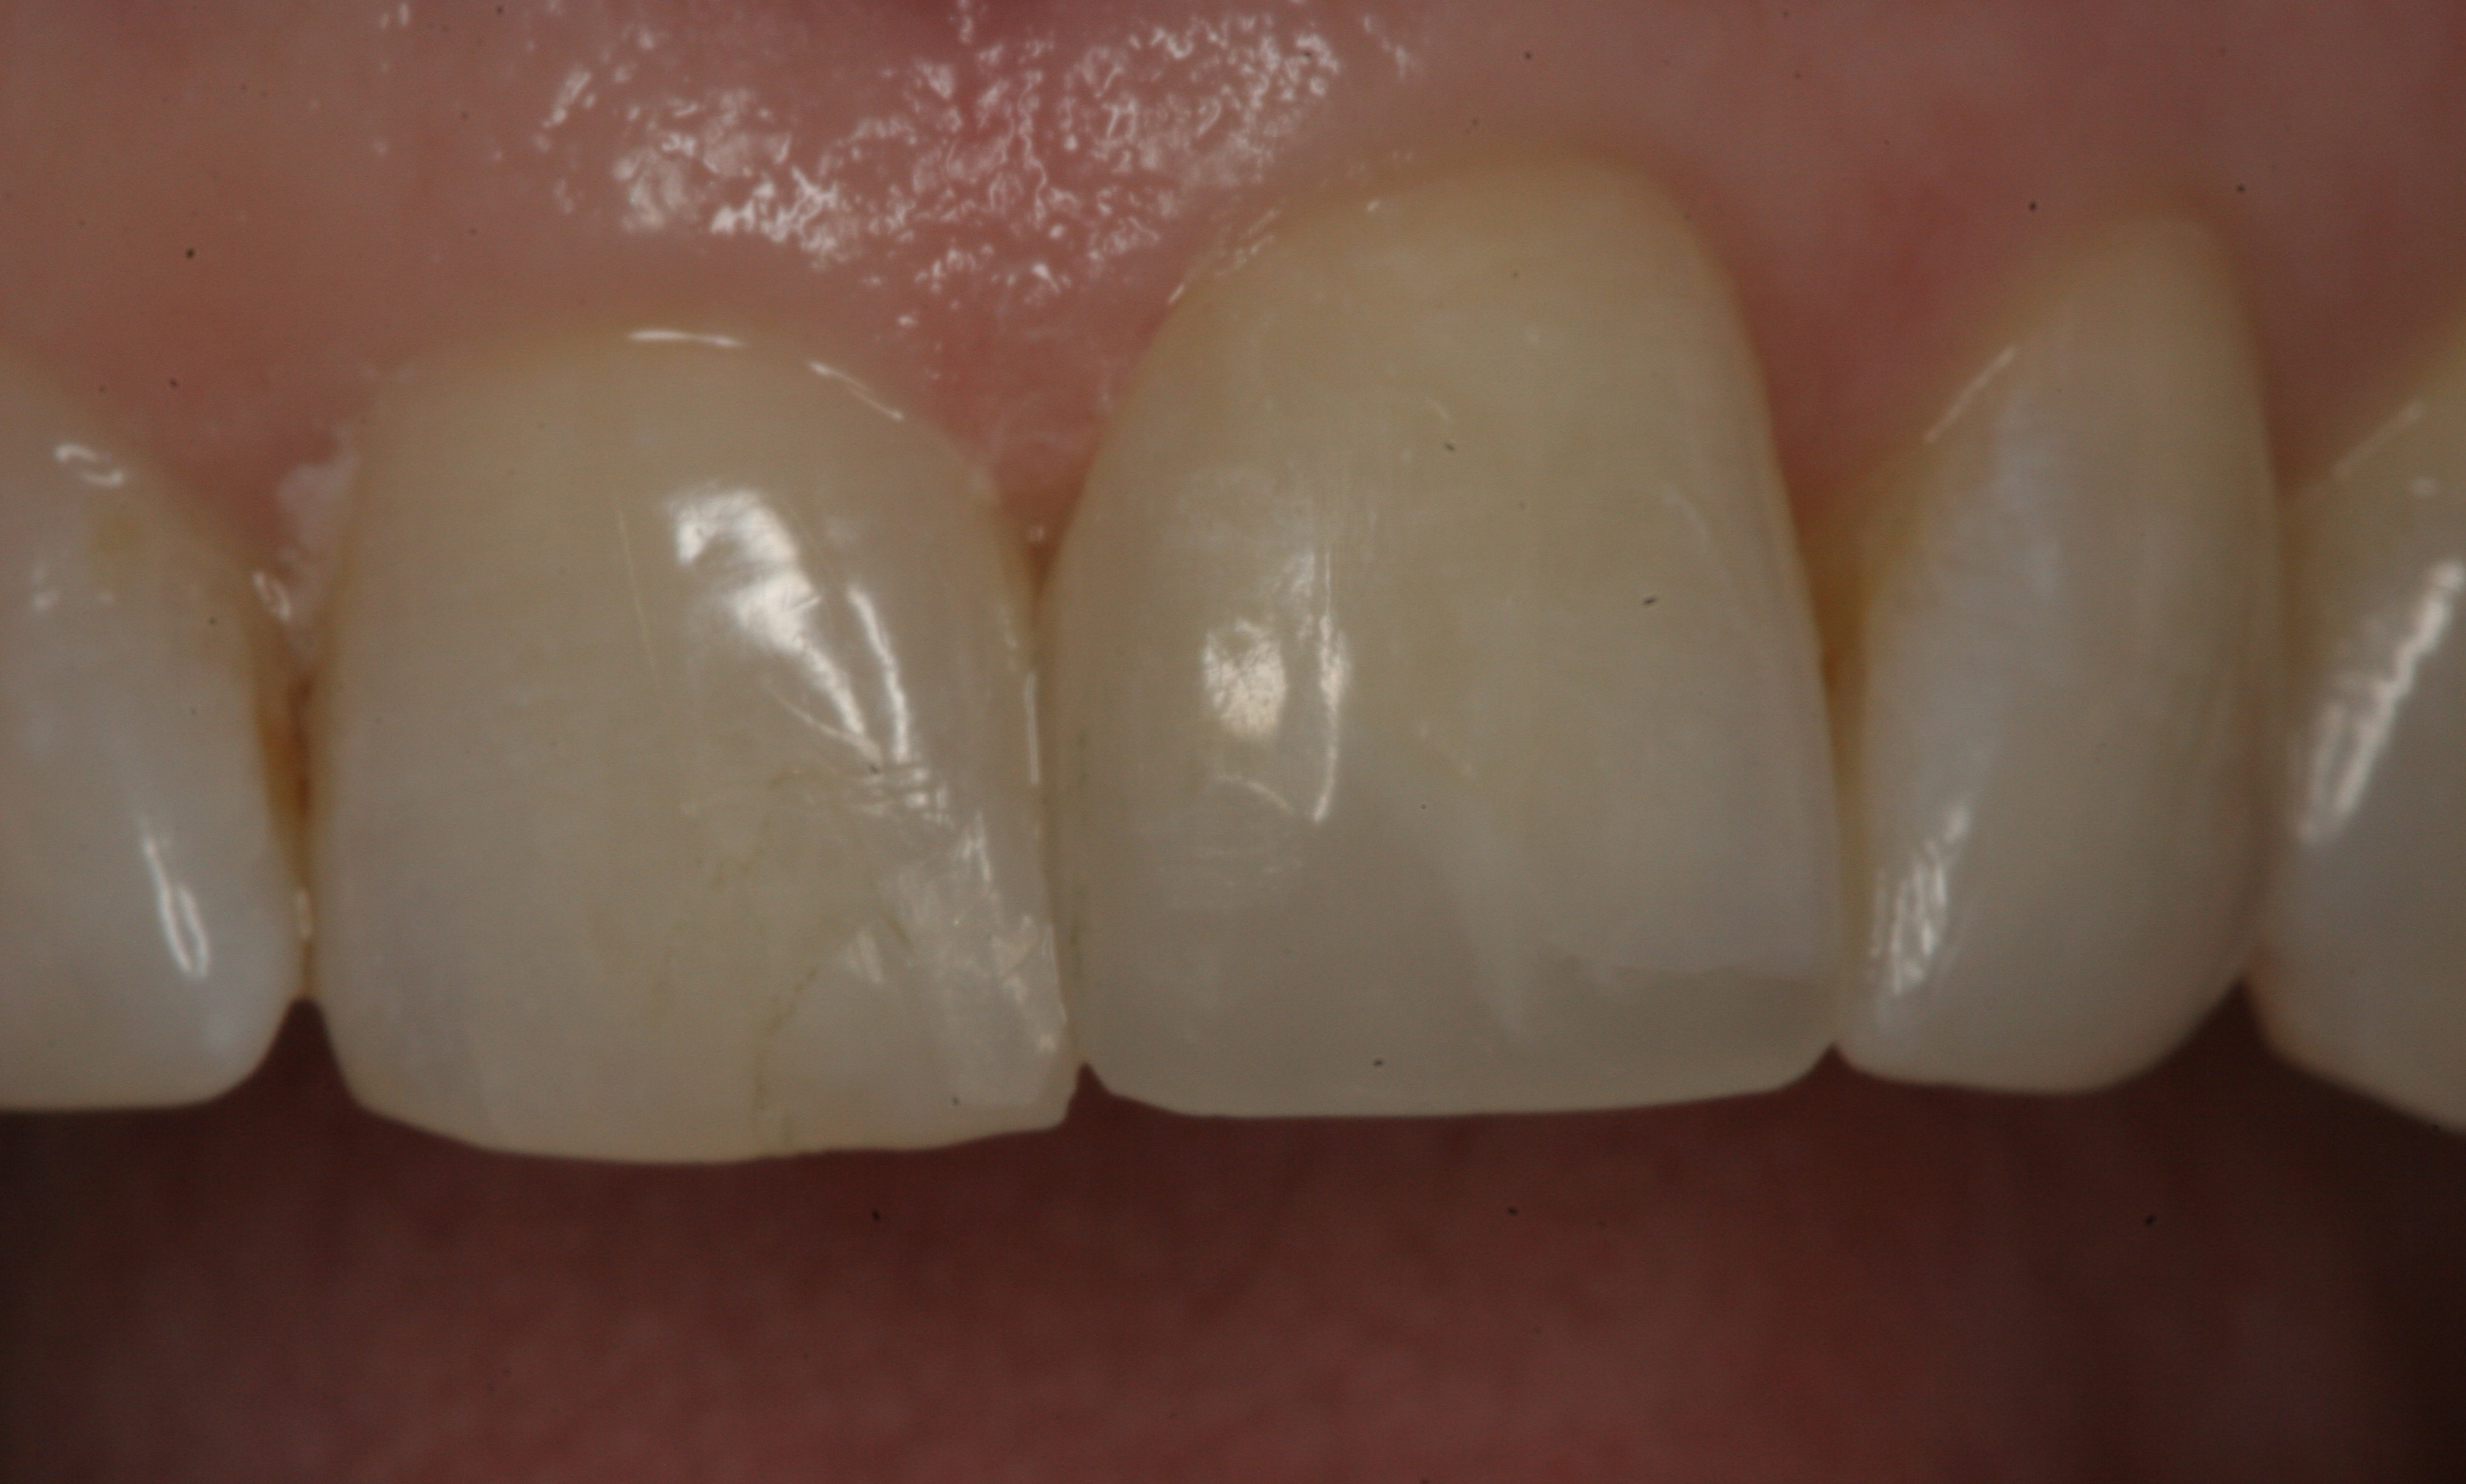

Fig 4. Preoperative view of a maxillary left central incisor after a traumatic incident that had caused loss of the mesial and incisal portion of the tooth.

Figure 4

Fig 5. Postoperative view of the restored tooth using a smart-matching resin composite without using a mirror-backing technique. Note the lower value of the incisal edge.

Figure 5

In restorative cases where a large portion of the incisal edge is missing or when extending the length of an anterior tooth is required, it is suggested that a lingual wall or "mirror-backing" be created to manage the translucency projecting the darkness from the back of the mouth (Figure 4 and Figure 5).40 The technique involves building a wall on the lingual aspect of the restoration with the opaque shade. This creates a less translucent lingual aspect that blocks the darkness from the back of the mouth and thus prevents it from showing through. After this wall is constructed, the more translucent smart-matching material can be applied to the front of the wall.